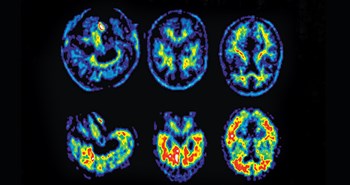

Han kom derfor endelig til lægen, hvor de blev enige om, at Per skulle have foretaget nogle scanninger. Resultaterne lod dog vente på sig, og da de så endelig kom, så var svaret ikke entydigt. Per blev derfor sendt videre til hukommelsesklinikken på Herlev Hospital, hvor de fik foretaget nye scanninger. Svarene på prøverne fik de dog først, da Per blev indlagt, fordi han pludseligt fik et ildebefindende, hvor Per var ved bevidsthed, men slet ikke var til at komme i kontakt med.

- Så kom der en læge hen til mig og sagde, at han ville gå ud og kigge på scanningsbillederne, som vi jo ikke havde fået svar på. Han kom så ind og sagde, at det ikke så godt ud. Han fortalte, at Pers hjerne ikke kunne mere lige nu, fordi han havde overkompenseret i lang tid. Han kunne nok godt forbedre sig igen, men han ville aldrig komme tilbage til samme niveau som før.

Per var de kommende fem dage indlagt på hospitalet, hvorefter han blev sendt direkte på aflastning på et plejehjem. De blev efterfølgende overført til Rigshospitalets hukommelsesklink, hvor lægen fortalte, at der var tydelige markører for Alzheimers sygdom.

Nu kunne Per og Minna altså ikke løbe fra det længere. Per blev diagnosticeret med Alzheimers sygdom.